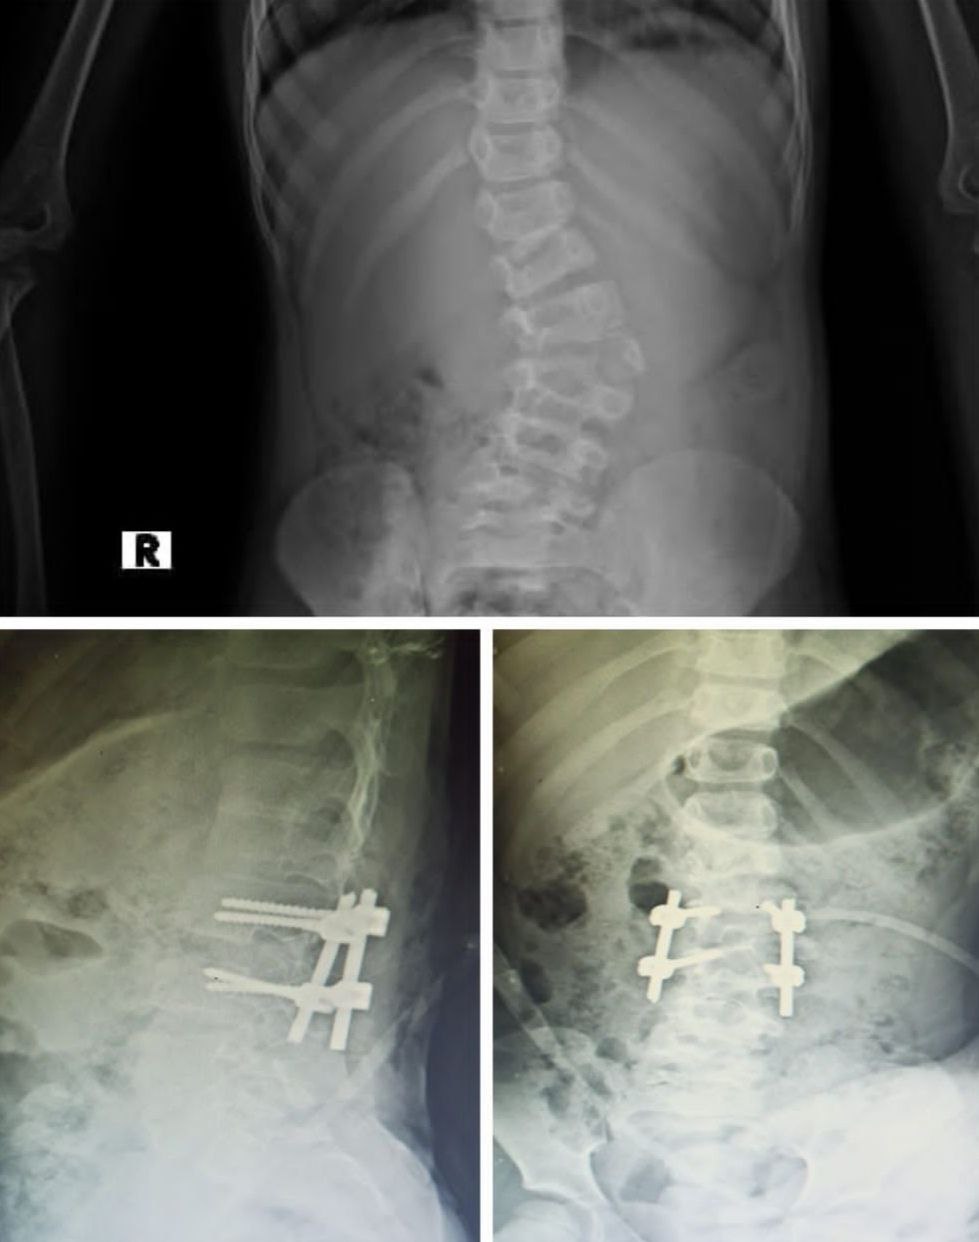

تعديل جنف و حدب

بفضل التعاون المثمر بين شركتنا والدكتور [علي السلوم]، تم تنفيذ عملية تعديل جنف متقدمة باستخدام أحدث تقنيات تثبيت العمود الفقري وبراغي عالية الدقة من شركتنا. النتيجة: تصحيح مثالي للمحور الفقري مع مظهر جراحي أنيق وتقنية تثبيت دقيقة تعكس جودة منتجاتنا وخبرة الطبيب العالية